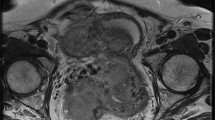

In the torsed ovary, the mean ADC value was significantly lower than that of the non-torsed ovary (mean 1.39 ± 0.58 × 10−3 mm2/s vs. 2.81 ± 0.17 × 10−3 mm2/s; p < 0.001). Also, the ADCs were significantly lower in patients with haemorrhagic infarction (n = 15, 1.03 ± 0.56 [×10−3 mm2/s]) than in those without (n = 14, 1.77 ± 0.31 [× 10−3 mm2/s]) (p < 0.001). The mean diameter of the torsed ovary was significantly larger than that of the non-affected ovary (mean 6.1 cm ± 0.79 vs 3.2 cm ± 0.62; p < 0.001). Using an ADC threshold of 1.27, the sensitivity of DWI for haemorrhagic torsion was 0.93 and specificity 0.85. A total of 20 patients (68.9%) had an ipsilateral accompanying mass. The histopathological diagnosis of the masses were as follows: follicular cyst (n = 3, simple; n = 4, haemorrhagic; Fig. 2), serous cystadenoma (n = 5), mucinous cystadenoma (n = 4), mature cystic teratoma (n = 2), endometrial cyst (n = 1) and granulosa cell tumour (n = 1; Fig. 3).

A female patient with left lower quadrant pain for 4 days. She was proved to have haemorrhagic ovary torsion due to granulosa cell tumour. a T2-weighted coronal MRI reveals an enlarged and oedematous left ovary (arrows) with an acompanying central mass. b T2-weighted axial MRI shows twisted pedicle sign (arrows) and central mass. c b 1000 image shows diffuse hypointensity of the enlarged ovary. d ADC map shows diffusion restriction of the peripheral stroma of ovary (ADC value, 0.74 × 10−3 mm2/s)